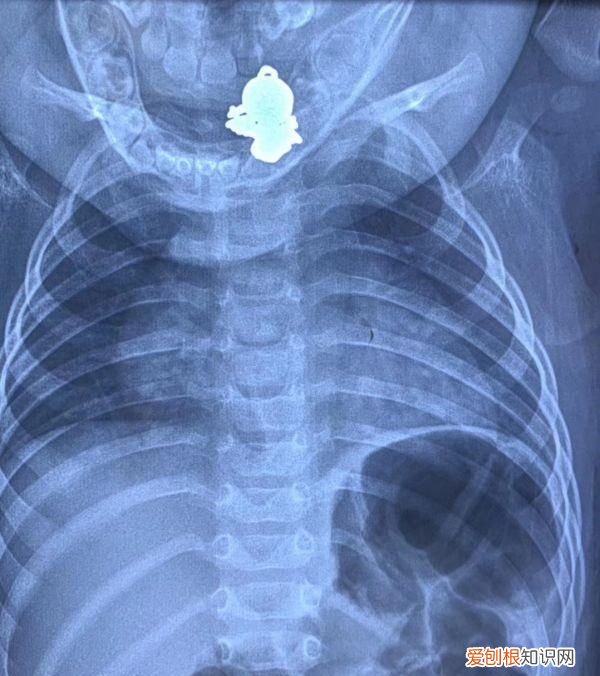

【解雨臣的四只吞金兽分别是谁 9个月的吞金兽吞下个金宝宝】嘟嘟吞下的“金宝宝” 。图由医院提供

拍片显示,吊坠卡在嘟嘟食道入口处 。图由医院提供